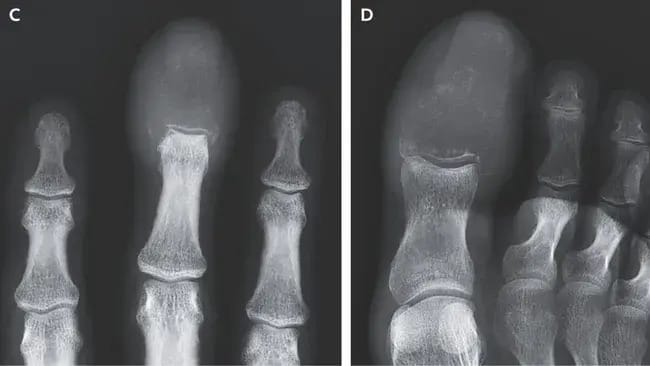

When Swollen Fingers Signal More Than Gout

A Case That Challenges Clinical Instinct

A New England Journal of Medicine case (July 2025) highlights a critical lesson:

Patient: 55-year-old man

Presentation: Swollen fingers and toes

Initial Diagnosis: Gout, following the principle “common things are common”

Six weeks later, X-rays revealed something shocking: the patient’s phalanges had virtually disappeared.

Not gout. Not arthritis. It was a rare (0.1%) presentation of lung cancer metastasis, aggressively eroding bone.

Further Reading

LiveScience Summary: Weird swelling revealed late-stage cancer